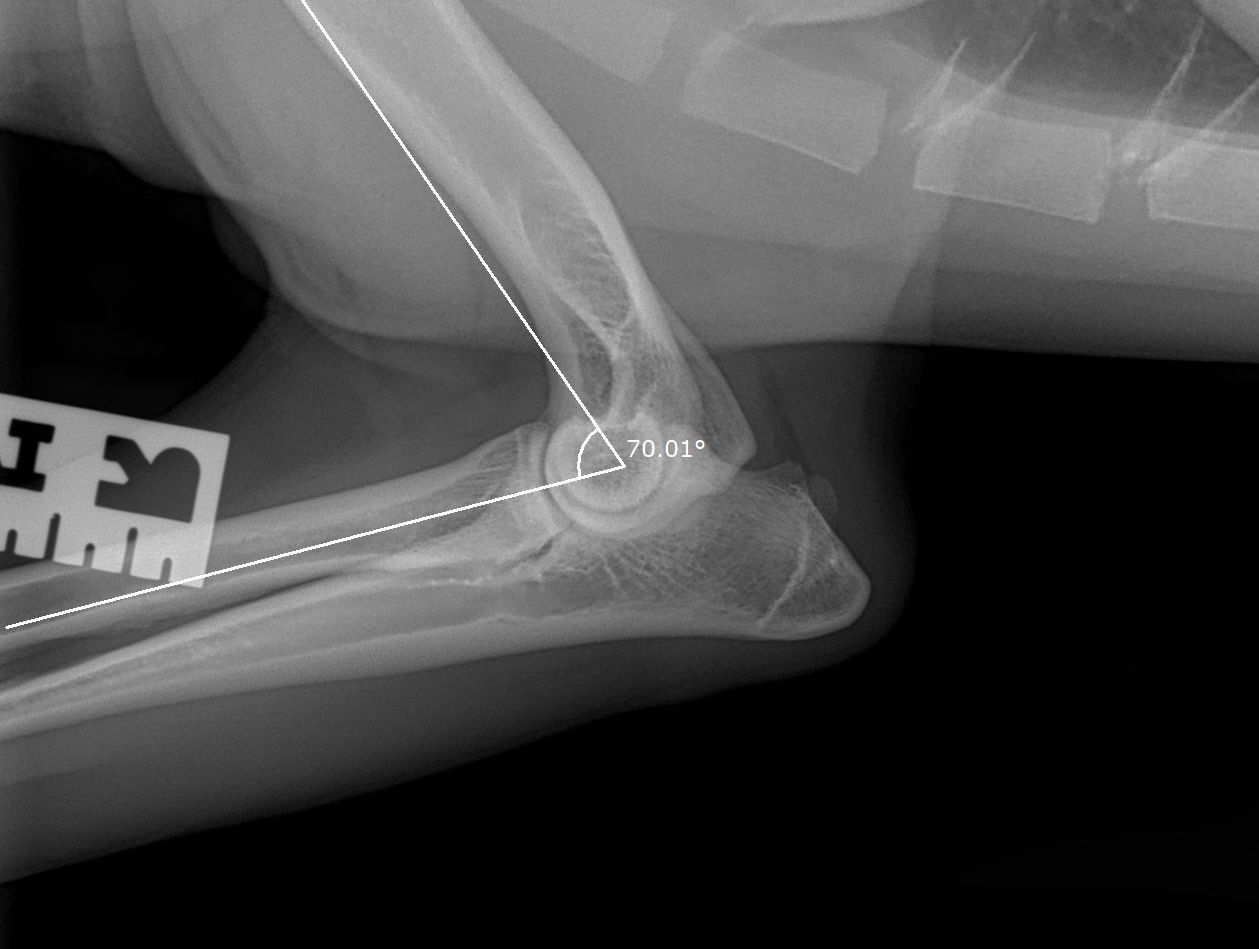

Hieronder foto's van Guus genomen met onze nieuwe DRgem rontgen. Beoordeeld met de hoogste score door de Raad van Beheer op Kynologisch gebied

Elleboogdysplasie (ED) onderzoek

Elleboogdysplasie is een ontwikkelingsstoornis van de ellebooggewrichten, met name het kraakbeen is aangetast. Deze aandoening kan erfelijk zijn, maar omgevingsfactoren spelen soms ook een rol. Er zijn honden die op jonge leeftijd al problemen ondervinden door ED, soms komt het pas op latere leeftijd tot uiting. Om te kunnen zien of uw hond ED heeft zijn röntgenfoto’s van de ellebogen nodig.

Voor alle andere rassen volstaat een onderzoek met twee foto’s per elleboog. Meestal passen wij een lichte sedatie toe bij het maken van de officiële ED-foto’s. Dit is nodig om een kwalitatief goede foto te maken, welke aan de hoge eisen van de beoordelingscommissie moet voldoen. Uw hond moet op zijn of haar zijde en borst liggen, waarbij de elleboog in verschillende houdingen wordt gelegd.